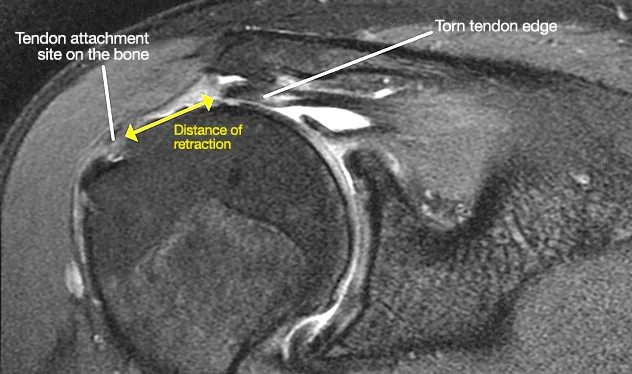

회전근개증후군 단계에서 적절한 치료를 받지 않으면 힘줄이 점차 얇아지다가 결국 끊어지는 파열로 이어집니다.

1️⃣ 부분 파열: 힘줄의 일부가 손상되어 통증과 약화가 시작됩니다.

2️⃣ 완전 파열: 힘줄이 완전히 끊어져 팔을 스스로 들기 어려워집니다.